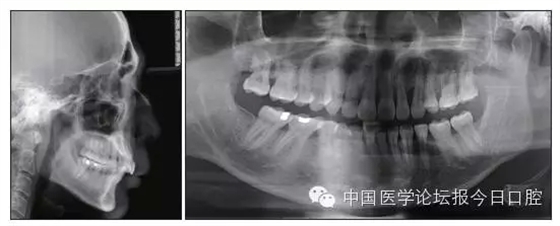

本病例為慢性牙周炎致前牙漂移、深覆(牙合)患者。本病例采用無托槽隱形矯治技術(shù)進行治療。無托槽隱形矯治器具有可摘戴、便于口腔衛(wèi)生維護和牙周治療的優(yōu)點,更適合于伴有牙周炎的錯(牙合)畸形患者的治療。 患者男,48歲,前牙有縫、前突求診。 患者面部對稱,側(cè)面觀上頜前突,下頜后縮。 口內(nèi)情況:恒牙列,24、34、44缺失,磨牙Ⅲ類關(guān)系,上牙列散隙,上前牙扇形漂移。前牙深覆(牙合)、深覆蓋??谇恍l(wèi)生較差,11與12間牙齦乳頭紅腫,多個牙探診有牙周袋形成,11松動Ⅰ度,余切牙松動(-),患者面像及口內(nèi)像如圖1、2所示。 圖1 治療前面像 圖2 治療前口內(nèi)像 全口曲面體層片(圖3)顯示,患者全牙列牙槽骨吸收;根尖片(圖4)示11近中牙槽骨角形吸收已達根尖1/3,21牙槽骨嵴頂吸收至根1/2,23牙槽骨近中骨板角形吸收至根1/2。磨牙區(qū)骨嵴頂吸收3mm。治療前頭顱側(cè)位片見圖3,治療前ODS模型見圖5。 圖4 治療前根尖片 圖5 治療前ODS模型 牙型:安氏Ⅲ類。骨型:Ⅱ類。面型:上頜前突,下頜后縮。 問題列表為:①上牙列間隙;②上切牙病理性牙移位;③前牙深覆(牙合)、深覆蓋;④24、34、44缺失;⑤慢性牙周炎。 矯治目標包括:①排齊牙列,關(guān)閉牙列間隙;②改善前牙深覆(牙合)、深覆蓋;③改善牙周狀況。 矯治設(shè)計有:①牙周基礎(chǔ)治療與維護。②壓低、內(nèi)收上切牙,關(guān)閉上牙列間隙。③壓低下切牙,伸長下后牙,整平Spee曲線,改善前牙覆(牙合)、覆蓋。 患者進行全口齦上潔治、齦下刮治,口腔衛(wèi)生宣教,并按牙周醫(yī)師的要求,每2~3個月行牙周檢查與治療。 牙周基礎(chǔ)治療結(jié)束3個月,開始隱形矯治。于14、25、35、36、45、46上粘接附件(圖6),于16、26(牙合)面粘接(牙合)墊。 圖6 ODS設(shè)計附件粘接圖示 矯治過程中注意(牙合)墊是否脫落或磨損,及時修補。 注意上前牙內(nèi)收時有無咬合干擾,及時調(diào)(牙合)。下頜前磨牙伸長到位后,磨除16、26(牙合)墊。 下頜佩戴第24步矯治器時,分別在36、37、46、47的頰、舌側(cè)粘接舌扣,矯治器上預(yù)留伸長空間,用3/16英寸、3.5盎司皮圈牽引,輔助伸長下磨牙(圖7)。 患者共戴用矯治器上頜32步,下頜26步。 矯治后,牙列間隙關(guān)閉,面型及覆(牙合)覆蓋改善。11根尖片(圖8)顯示,治療后較治療前,牙周支持組織增加,牙槽骨角形吸收區(qū)水平向縮小0.3mm,垂直向縮小0.6mm。11松動Ⅰ度,余切牙無松動。 圖8 治療后根尖片 圖9 治療后口內(nèi)像 圖10 治療后X線檢查 圖11 治療后ODS模型 正畸-牙周聯(lián)合治療對于牙周組織的影響 多學(xué)科綜合治療牙周炎患者不再是正畸治療的禁忌證。良好的牙周治療為正畸治療中的牙齒移動打下堅實基礎(chǔ),而正畸治療排齊牙齒、去除(牙合)干擾,有利于牙周健康。 牙周炎患者的正畸治療必須在牙周炎癥得到控制后才能進行,否則,菌斑會隨著牙齒的移動,特別是壓低而使牙周炎癥加重。牙周炎的正確診斷、牙周炎癥控制、正畸治療中和治療后的認真維護是治療成功的關(guān)鍵。根據(jù)臨床需要,一般每2~4周做一次潔治,每3個月進行牙周評估,同時患者必須進行非常良好的日??谇恍l(wèi)生維護。 固定矯治器使得牙周檢查、潔治和日??谇恍l(wèi)生維護變得困難,隱形矯治器可自行摘戴,便于患者日常維護和牙周治療,節(jié)約時間,提高菌斑控制效果。 有臨床研究表明,對于存在(牙合)創(chuàng)傷,伴有角形吸收的患牙,經(jīng)過牙周翻瓣手術(shù)控制住牙周炎癥后,使用正畸輕力壓低患牙,可以改善牙槽骨吸收的程度,并獲得一定程度的牙周新附著。本病例切牙壓低后,原來的牙槽骨吸收有改善。 病理性牙移位 病理性牙移位(PTM)在重度牙周炎患者中的發(fā)生率為30%~50%,且常見于上前牙區(qū)。其主要由于牙周支持組織喪失尤其是骨組織的丟失,咬合因素(如后牙缺失、前牙深覆牙合、牙合創(chuàng)傷等),頰舌唇肌力量不平衡及牙周和根尖周組織炎癥所致,是牙周炎患者要求正畸治療的主要原因之一。 PTM須通過正畸、牙周聯(lián)合,有時須配合修復(fù)才能達到理想的治療效果。正畸治療通常是壓低牙齒,臨床研究表明,牙周手術(shù)配合正畸壓低可以產(chǎn)生新附著,有利于PTM牙周組織的恢復(fù)。 本病例右上中切牙牙槽骨角形吸收,在盡量保證治療前后根尖片投照角度一致的情況下,以鄰牙作為校準,在根尖片上對治療前后的骨量進行評價,治療后牙槽骨角形吸收區(qū)水平向縮小0.3 mm,垂直向縮小0.6mm。盡管根尖片并不能說明骨量改變,但從影像學(xué)上能看到骨吸收區(qū)域有所減小。 無托槽隱形矯治器矯治牙周病的優(yōu)勢 無托槽隱形矯治器具有可摘戴、便于口腔衛(wèi)生維護和牙周治療的優(yōu)點,更適合于伴有牙周炎的錯(牙合)患者的治療;同時,無托槽隱形矯治器佩戴后具有牙弓夾板和(牙合)板的作用,可有效減少側(cè)向力,有利于牙周的恢復(fù)和減輕牙齒松動;由于無托槽隱形矯治器的設(shè)計是在三維數(shù)字模型上進行的,每個矯治器移動牙齒的數(shù)量和每個牙齒的移動距離可以得到量化控制,因而可以根據(jù)患者牙槽骨水平和對矯治力的耐受情況個性化設(shè)計矯治力,并且可以根據(jù)矯治中牙齒移動情況調(diào)整后續(xù)矯治器的設(shè)計。 有關(guān)磨牙伸長 單純使用無托槽隱形矯治器同步伸長后牙比較困難。該病例先使用磨牙(牙合)墊打開咬合,通過矯治器伸長前磨牙,在前磨牙建立咬合后,磨除磨牙上的(牙合)墊,通過輔助牽引伸長磨牙,最終達到伸長后牙、整平Spee曲線的目的。 史真,主任醫(yī)師,現(xiàn)任北京黃寺整形外科醫(yī)院口腔科主任,第四軍醫(yī)大學(xué)口腔正畸學(xué)碩士,為世界正畸醫(yī)師聯(lián)盟(WFO)會員、全軍口腔醫(yī)學(xué)專業(yè)委員會委員、中華口腔正畸專業(yè)委員會委員、中華醫(yī)學(xué)美學(xué)與美容學(xué)會齒科美容學(xué)組成員、北京口腔醫(yī)學(xué)會兒童口腔專業(yè)委員會常務(wù)委員、北京口腔醫(yī)學(xué)會正畸專業(yè)委員會委員、《中華醫(yī)學(xué)美學(xué)與美容》雜志審稿專家,是我國最早開展無托槽隱形矯治技術(shù)的口腔醫(yī)師之一。

圖3 治療前頭顱側(cè)位片及曲面體層片